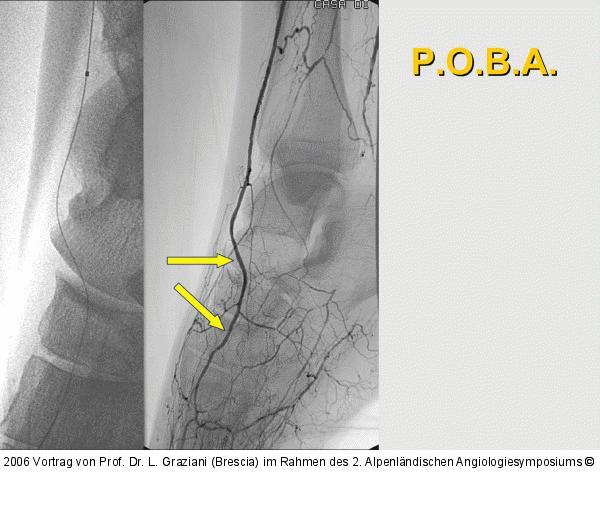

Vortrag von Prof. Dr. L. Graziani (Brescia) im Rahmen des 2. Alpenländischen Angiologiesymposiums

PTA of the foot arteries in diabetics: Extremities Extreme Angioplasty

Abbildung 58: P.O.B.A.